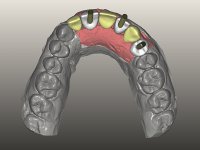

O paciente foi observado conjuntamente e a dúvida que surgiu de imediato foi se seria possível com a regeneração óssea a efectuar poder ser reabilitada naturalmente a zona das papilas interdentárias. Nesse sentido foi feito um enceramento de diagnóstico que contemplaria as duas hipóteses, utilizando ou não a cerâmica gengival. A confecção desse enceramento foi fundamental para expor ao paciente a dificuldade da reabilitação. O wax-up deu origem a um mock-up que foi aprovado pelo paciente e que simultaneamente serviu de guia imagiológica. O caso foi planificado cirurgicamente e realizada uma guia cirúrgica com que foram colocados os implantes. Após 10 semanas foi feita a 1ª impressão para confecção da ponte provisória. Foram criados os primeiros perfis de emergência na gengiva artificial e foi digitalizado o modelo. Por processo de CAD-CAM foi confeccionada uma ponte provisória aparafusada baseada no enceramento de diagnóstico. A ponte trabalhou durante 8 semanas os tecidos moles que foram fielmente copiados numa impressão com técnica de moldeira aberta. Os transferes foram individualizados com resina composta para copiarem fielmente os perfis de emergência criados pela ponte provisória. Confeccionado o modelo de trabalho definitivo, foi realizada uma infra-estrutura em zircónio seguindo a orientação do enceramento de diagnóstico. O assentamento da infra-estrutura foi testado em boca e simultaneamente foi novamente impressionados os tecidos moles com um silicone fluido. Nessa consulta foi feito o levantamento da cor. Os dentes 13 e 23 apresentavam uma saturação anormalmente forte que resolvemos não valorizar, optando por privilegiar a relação com o sector antero-inferior. Foi realizada uma nova gengiva artificial com a impressão que acompanhou a impressão de arrasto com a infra-estrutura. Após a colocação da cerâmica na infra-estrutura foram coladas as meso-estruturas. O trabalho final foi aparafusado lentamente permitindo a adaptação dos tecidos moles.